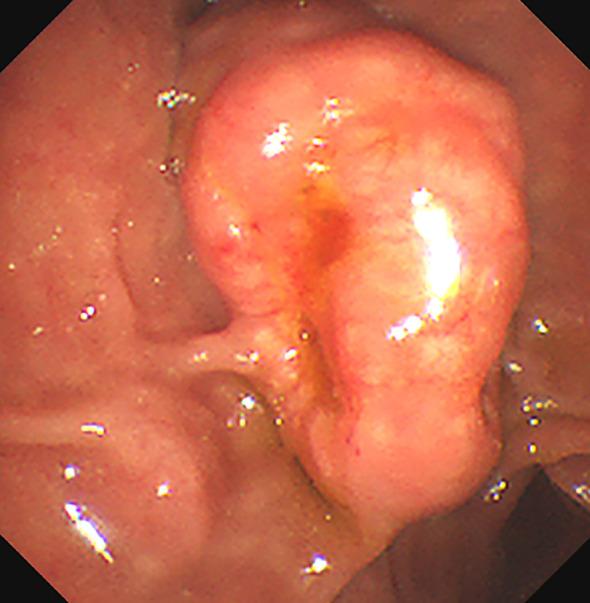

Neurofibromatosis type 1 (NF-1) is commonly associated with a variety of rare tumors. However, no case of multiple gastric gastrointestinal stromal tumors (GISTs) or duodenal ampulla neuroendocrine tumors (NETs) with multiple liver metastases in a patient with NF-1 has yet been reported. Here, we describe a case of a 55-year-old female patient with NF-1 whose serum Pro-Gastrin-Releasing Peptide (pro-GRP) levels were elevated. Gastrointestinal endoscopy and biopsy showed duodenal papilla space-occupying mass, and the pathological diagnosis turned out to be neuroendocrine tumors (NETs). During surgical exploration, multiple tumors were found on the serosal surface of the stomach and numerous miliary metastases in the liver. Following histopathological examination, it was determined that the liver metastases were NF-1 and the tumors in the gastric wall were GISTs. The patient benefited from targeted therapy and had an uneventful hospital stay. In this case, we emphasize treating patients with neurofibromatosis type 1 who exhibit abdominal symptoms with a high degree of clinical suspicion and performing thorough evaluations to rule out multiple tumors.

1型神经纤维瘤病(NF-1)通常与多种罕见肿瘤相关。然而,尚未有关于1型神经纤维瘤病患者出现多发胃胃肠道间质瘤(GISTs)或十二指肠壶腹神经内分泌肿瘤(NETs)并伴有多发肝转移的病例报道。在此,我们描述了一名55岁患有NF-1的女性患者,其血清胃泌素释放肽前体(pro-GRP)水平升高。胃肠内镜检查及活检显示十二指肠乳头占位性肿块,病理诊断为神经内分泌肿瘤(NETs)。手术探查时,在胃浆膜表面发现多个肿瘤,肝脏有大量粟粒样转移灶。经组织病理学检查,确定肝脏转移灶为NF-1,胃壁肿瘤为GISTs。该患者受益于靶向治疗,住院期间病情平稳。在此病例中,我们强调对于出现腹部症状的1型神经纤维瘤病患者要高度临床怀疑,并进行全面评估以排除多发肿瘤。